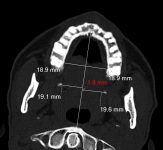

إنفاذًا لتوجيهات #وزير_الدفاع.. إجراء عملية جراحية لطفلة سودانية بـ #مركز_الأمير_سلطان_للقلب

صراحة – الرياض : إنفاذًا لتوجيهات صاحب السمو الملكي وزير الدفاع، الامير خالد بن سلمان نجح فريق طبي متخصص من مركز الأمير سلطان لمعالجة أمراض وجراحة القلب للقوات المسلحة في إجراء عملية جراحية دقيقة لطفلة…

إنهاء معاناة مريضة بـ”سعود الطبية” من آلام مزمنة في الوجه والبلع